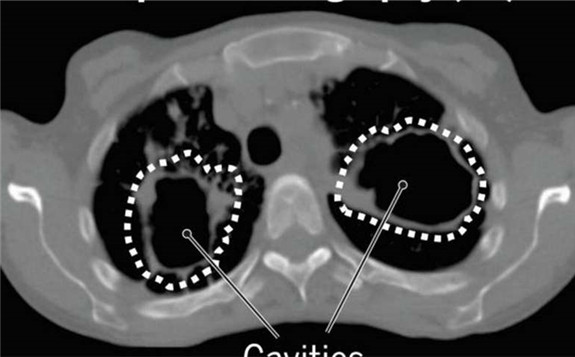

使用PET和CT扫描可能有助于缩短结核病的治疗时间

结核病已成为人类的祸害,已有约15,000年之久,该病的第一批医学文献出自印度,大约在公元前1000年。今天,世界卫生组织报道,结核病仍是主要的死亡原因在全球范围内,由一个传染病媒介负责,每年造成约150万人死亡。在过去的50年中,结核病的主要治疗方法没有改变,仍然需要患者至少六个月每天服用多种药物。这些抗结核药物的成功治疗-口服或注入血液-取决于药物“探寻途径”进入埋在肺部深处的结核菌的口袋。 2020-04-27